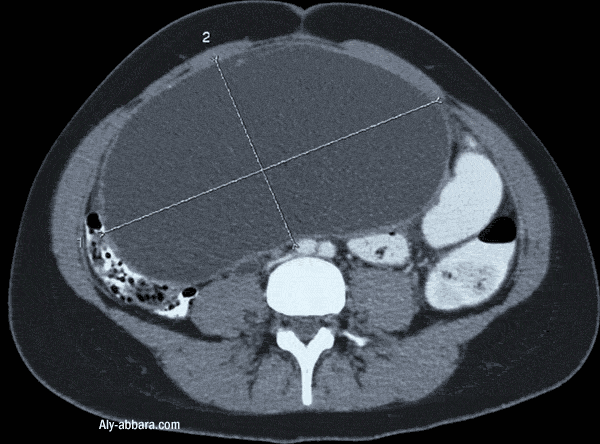

Volumineux kyste mucoïde bénin uniloculaire de l'ovaire gauche

Cystadénome mucineux bénin de 110 x 190 x 249 mm

contenant 3200 cc de liquide visqueux